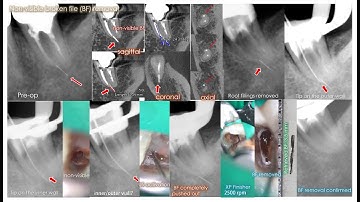

Removal of a nonvisible broken TFRK-12 tip beyond the severe curve